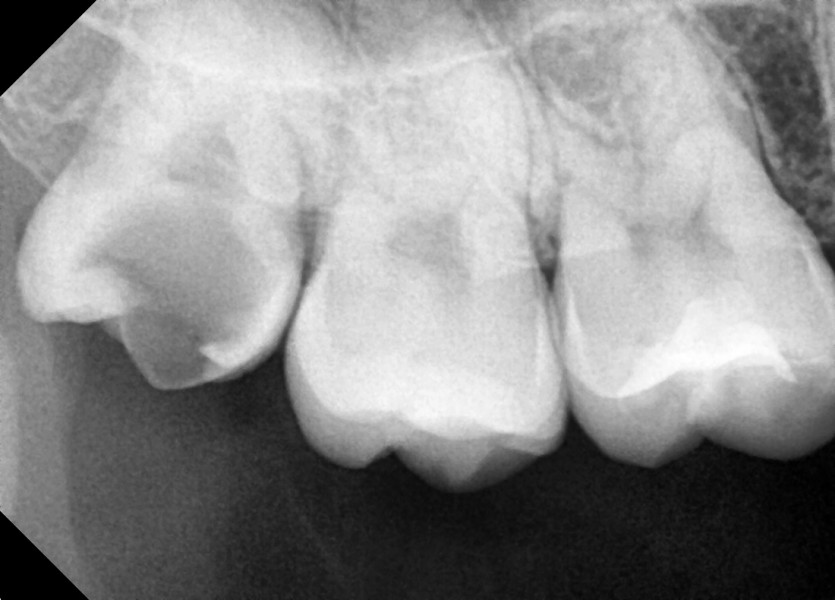

#18,48 사랑니 발치

구강 외과 전문의가 당일 발치했습니다.